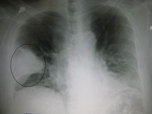

سینهپهلو یا ذاتالریه یا پنومونی (به فرانسوی: Pneumonie) یا نومُنیا (به انگلیسی: Pneumonia)، وضعیت التهابی ریه است که عمدتاً کیسههای میکروسکوپی هوا موسوم به آلوئولها را تحت تأثیر قرار میدهد. این بیماری معمولاً در اثر عفونت ناشی از ویروس یا باکتری و گاهی نیز در اثر سایر میکروارگانیسمها، برخی داروها و شرایط دیگر مانند بیماری خودایمنی رخ میدهد. در این بیماری، کیسههای هوایی متورم میشود و چون درون آن از مایعات پر میشود، در نتیجه اکسیژن رسانی کمتر میشود و تبادلات گازی کاهش مییابد.